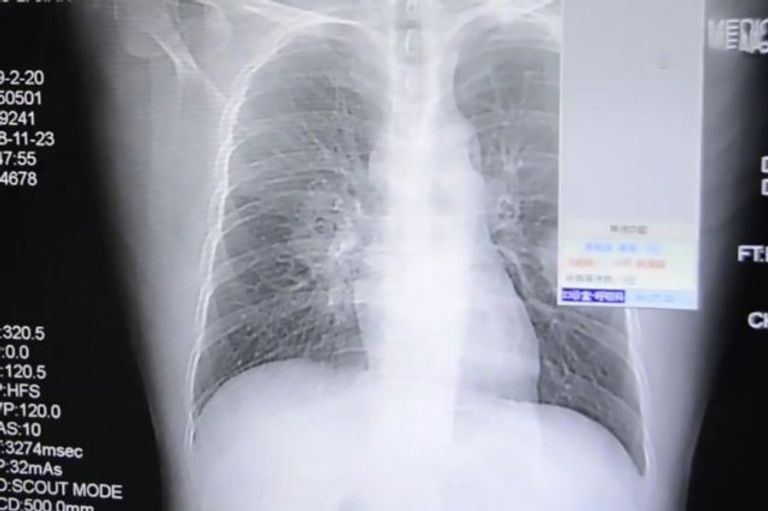

وأدخل الرجل، المعروف باسم بنغ، إلى المستشفى كحالة طارئة عندما بدأ في السعال بشكل سيئ وشهد آلامًا في الصدر، وبعد خضوعه للتصوير المقطعي بالأشعة السينية، أكد الطبيب أنه يعاني من التهاب شديد في الرئة.